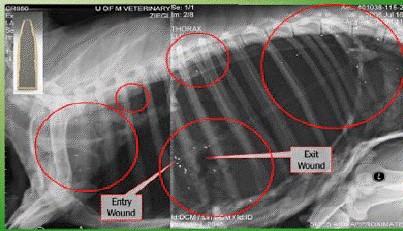

Photo courtesy of Minnesota Department of Natural Resources, Farmland Wildlife Populations and Research Group, 35365 800th Ave, Madelia, MN 56062

This is scary, too. An x-ray of a domestic sheep shot with lead ammo. Bullet fragments are within the red circles and throughout the body cavity and pelvic cavity, even though it was shot behind the shoulder blade.